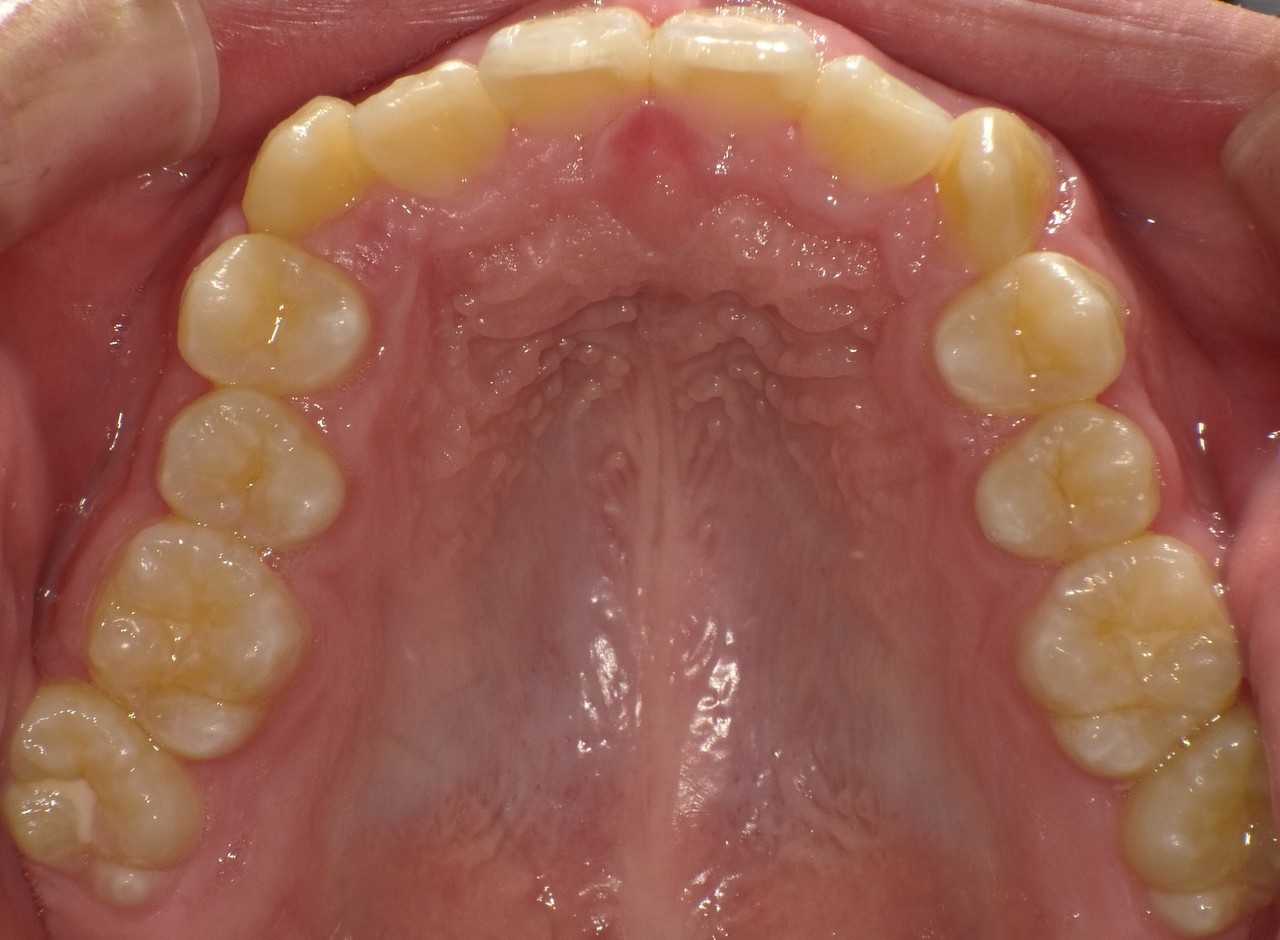

Before

After

矯正の種類 / invisalign GO

年齢・性別 / 40代女性

主訴  /  上下の叢生、開咬、オーバージェット

治療期間 / 12ヶ月

費用 / 簡易検査 5,000円(税別) 精密検査 30,000円(税別)

両額マウスピース 450,000円(税別) 両額リテイナー料 40,000円(税別)

※マウスピース交換時別途調節料5,000円(税別)

副作用 / 口内炎・歯の移動に伴う痛み・知覚過敏 ※数日で収まる場合が多いです

リスク / 後戻り防止の為、夜のみマウスピースで保定を指示